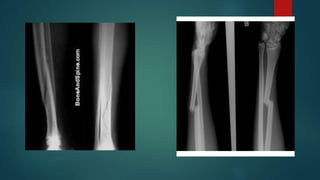

a. Transverse fracture:

 Fracture line is perpendicular to the long axis of the bone

 Caused by a tapping or bending force

 X- ray: fragments usually remains in place after reduction

b. Oblique fracture:

 Fracture line is oblique

 Caused by a bending force

 Has a component along the long axis of the bone

 X- ray: tend to shorten and re- displace even if the bone is splinted

c. Spiral fracture:

 Fracture line runs spirally in more than one plane

 Caused by a primarily twisting force

 X- ray: same as oblique fracture

ON THE BASISOF PATTERN 1. Complete fracture:  Bone is split into two or more fragments a. Transverse fracture:  Fracture line is perpendicular to the long axis of the bone  Caused by a tapping or bending force  X- ray: fragments usually remains in place after reduction b. Oblique fracture:  Fracture line is oblique  Caused by a bending force

 Has acomponent along the long axis of the bone  X- ray: tend to shorten and re- displace even if the bone is splinted c. Spiral fracture:  Fracture line runs spirally in more than one plane  Caused by a primarily twisting force  X- ray: same as oblique fracture d. Comminuted fracture:  Fracture with multiple fragments  Caused by a compression or crushing force along the long axis of the bone  X- ray: more than two fragments; unstable